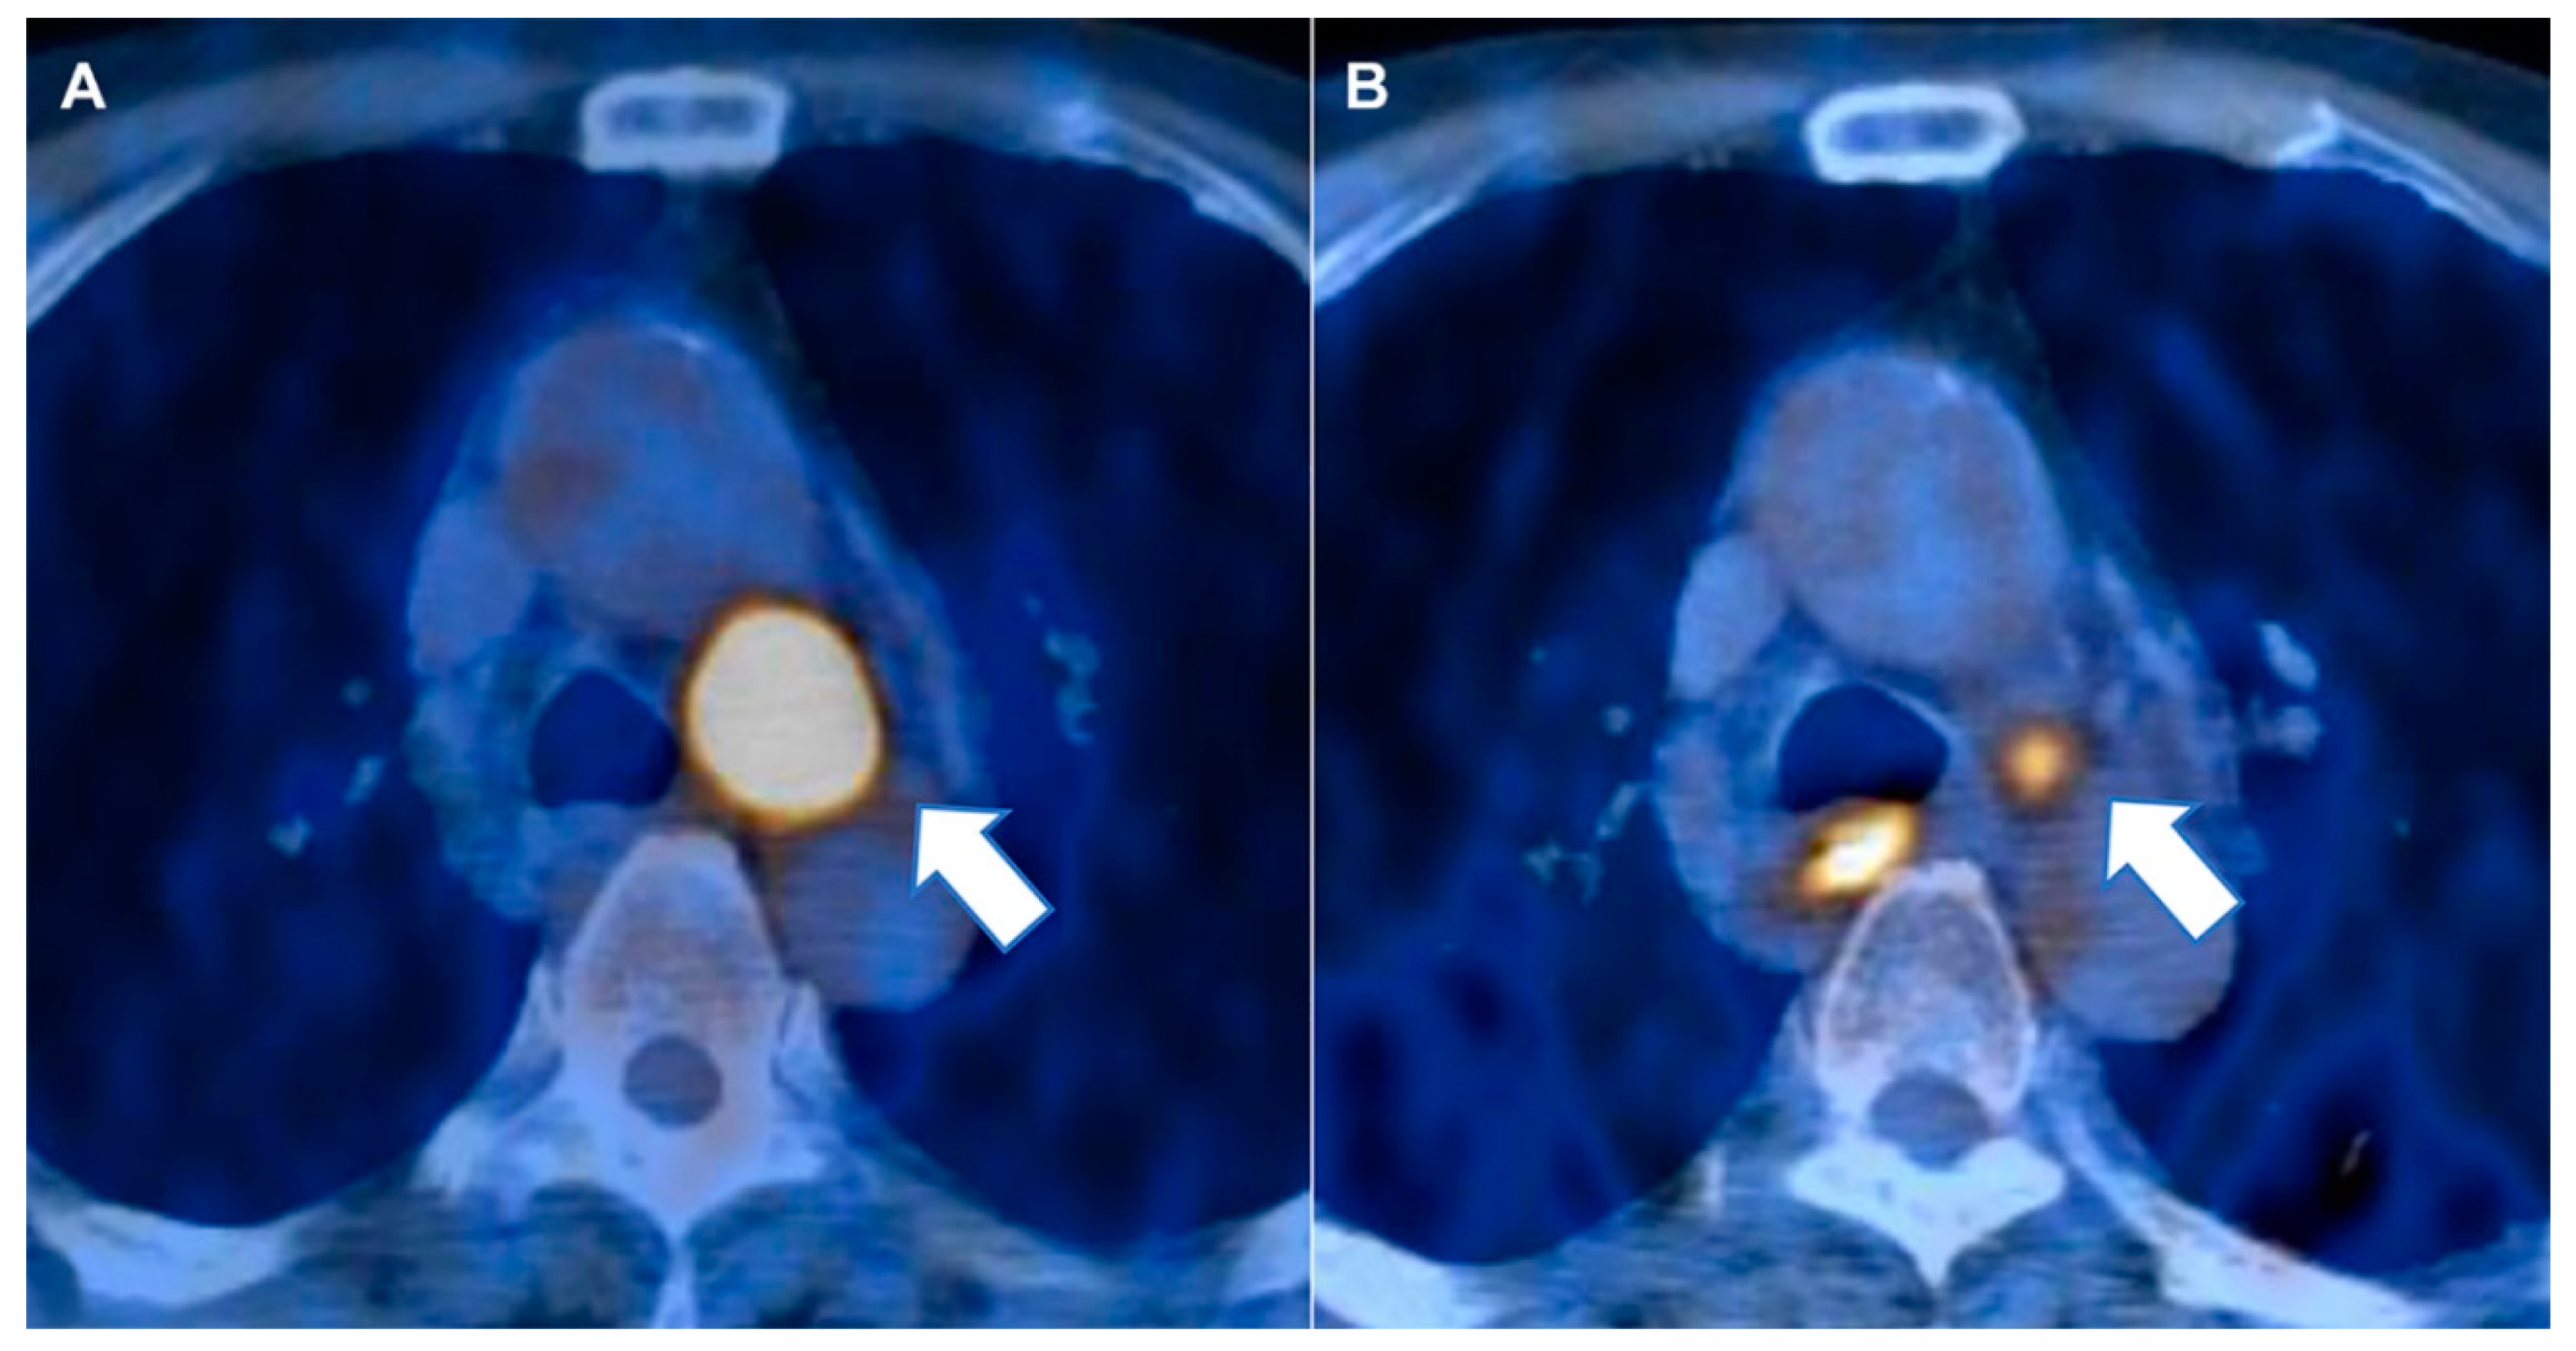

4.2. Image Analysis and Region of Interest Segmentation